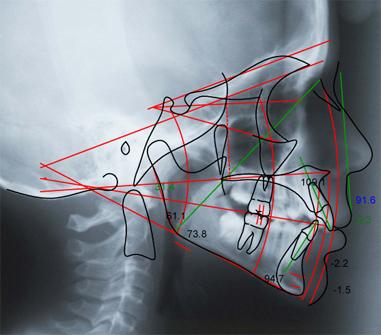

SML can print models for appliance fabrication, provide digital evaluation reports or archive your digital patient records for documentation purposes.